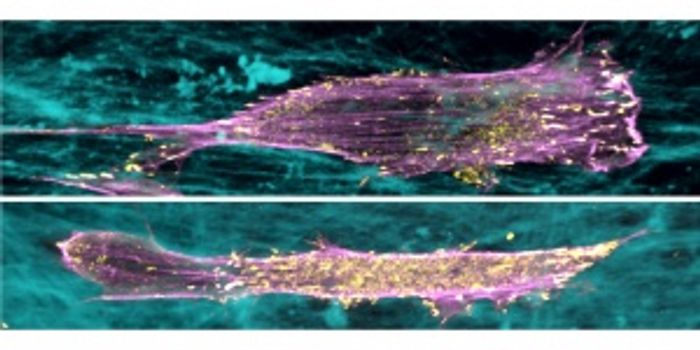

MAR 17, 2015ImmunologyResearchers at the University of Arizona have discovered what causes and regulates collective cell migration, one of the ...